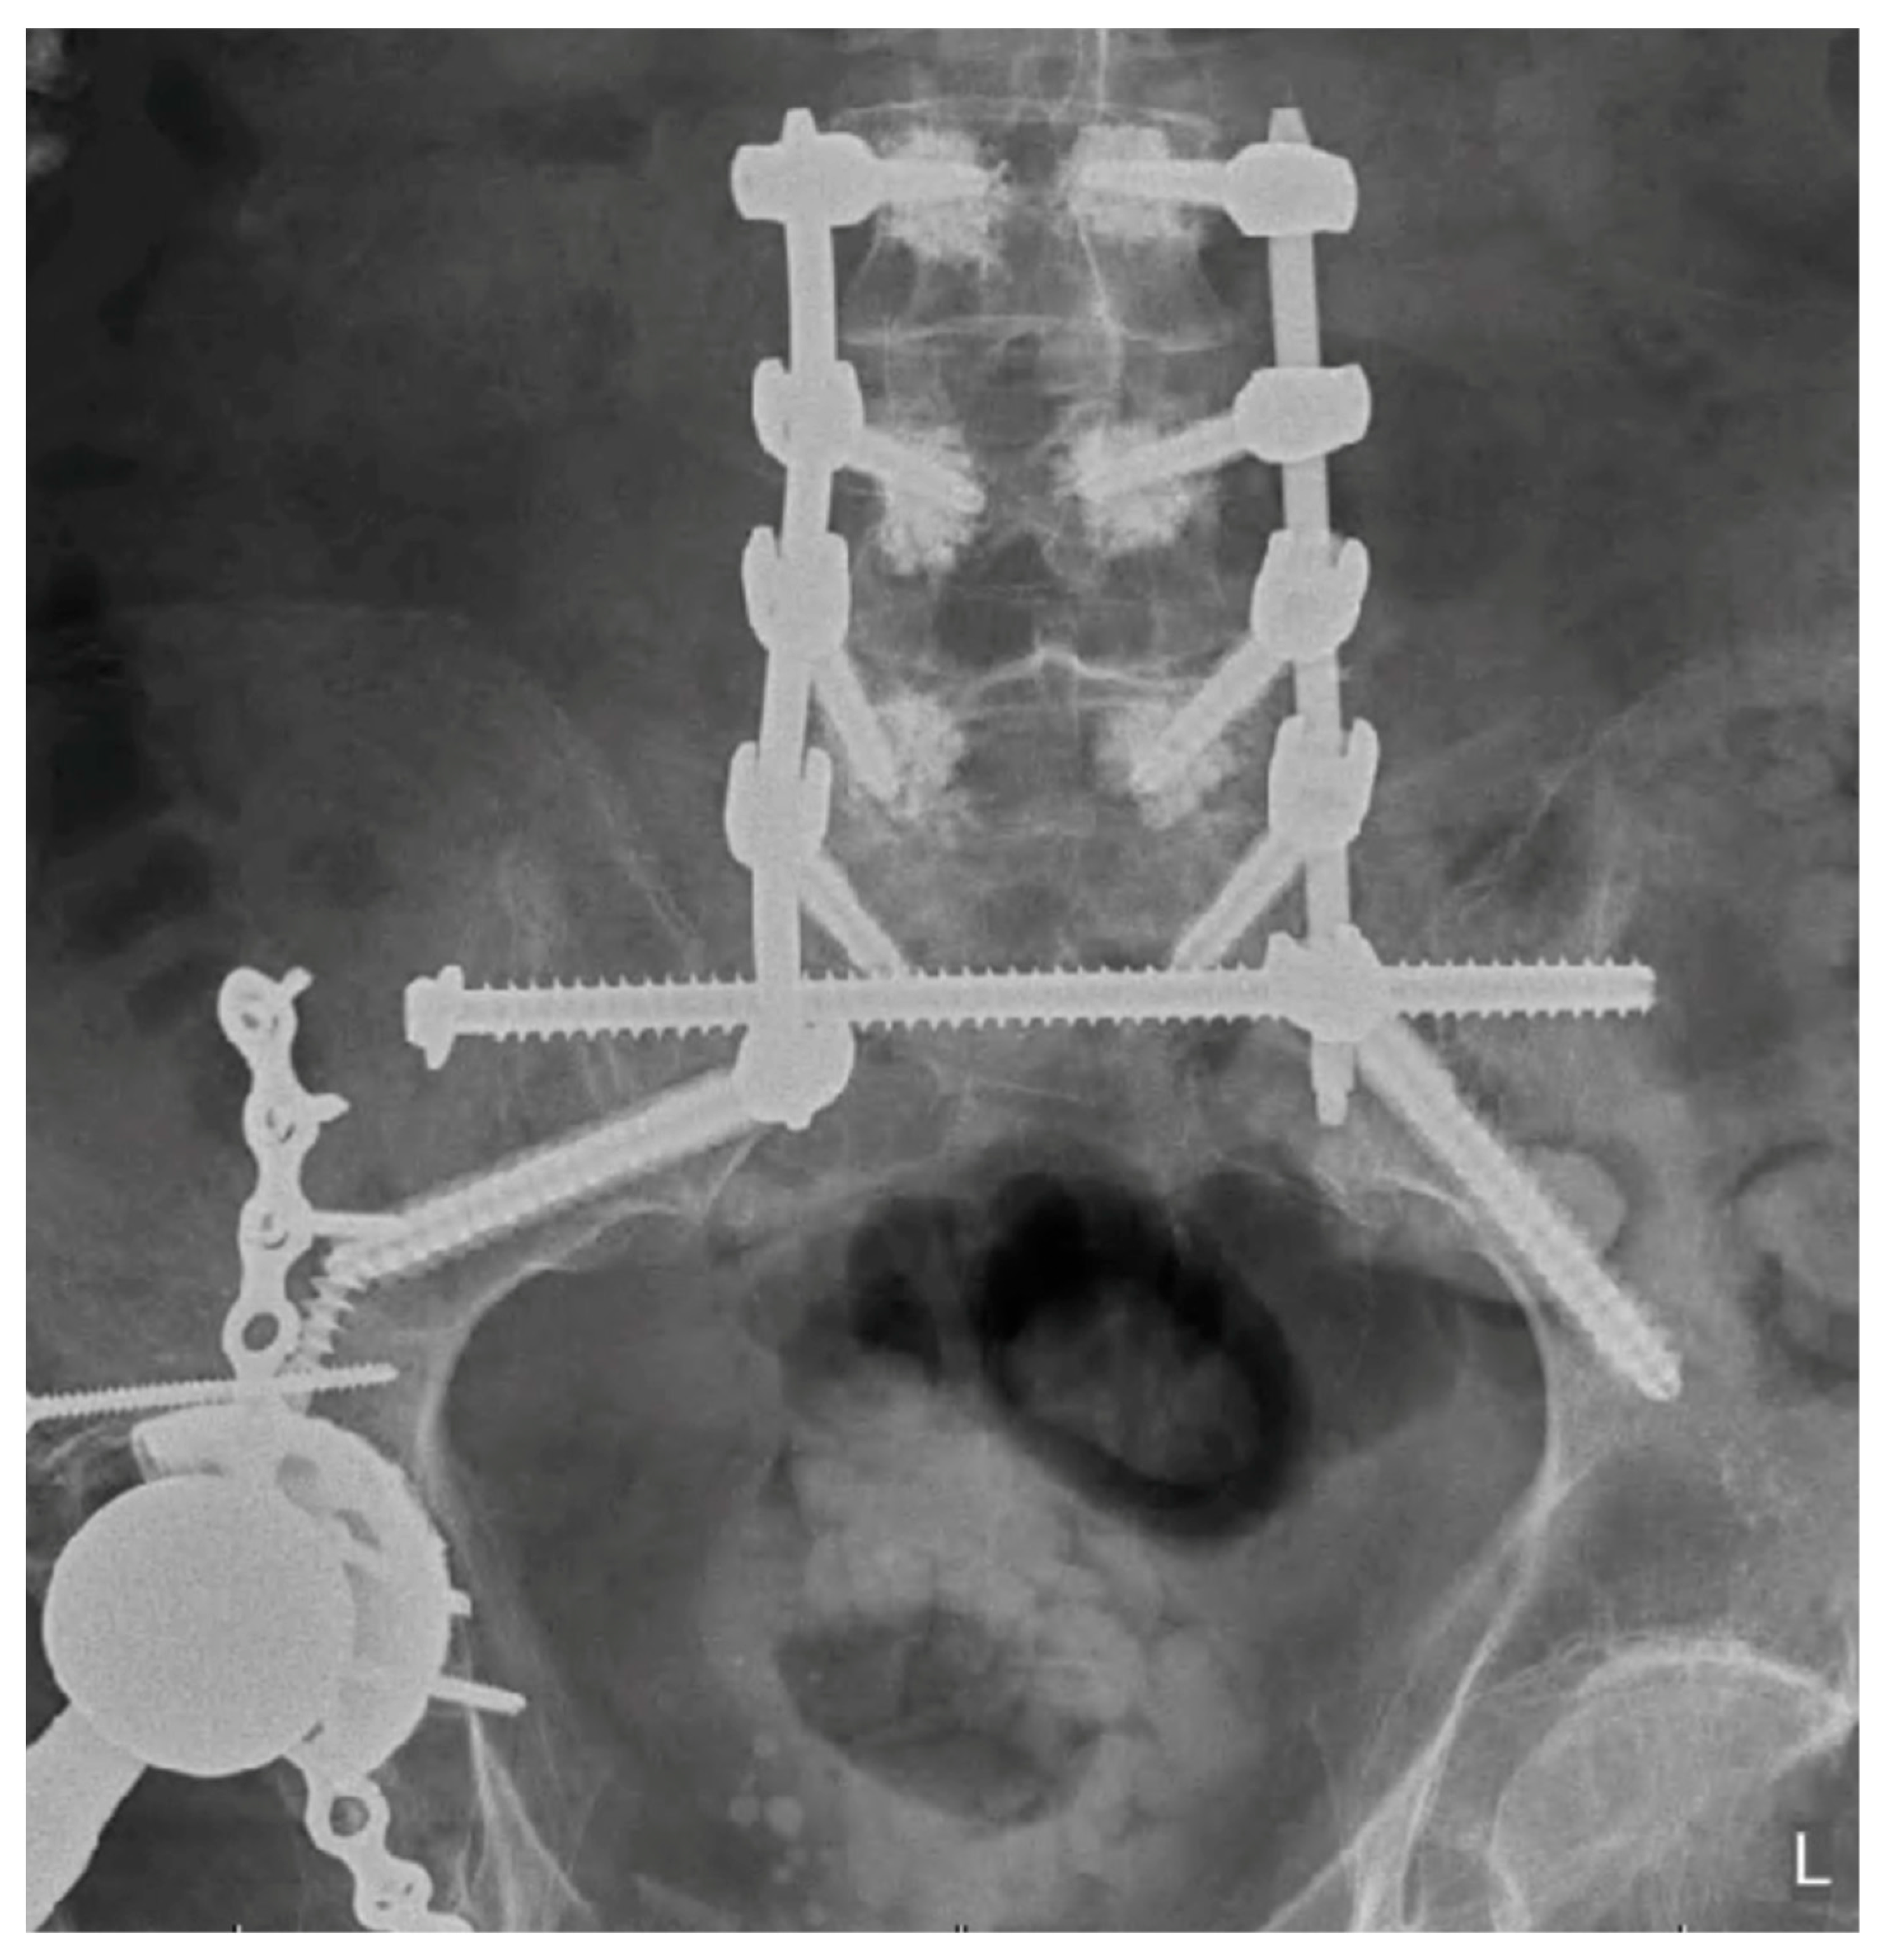

5. Techniques and Considerations in Spinopelvic Fixation: Sequence, Reduction, and Avoiding Complications

6. Spinopelvic Fixation Percutaneous Technique

7. Tran-Sacral Percutaneous Technique